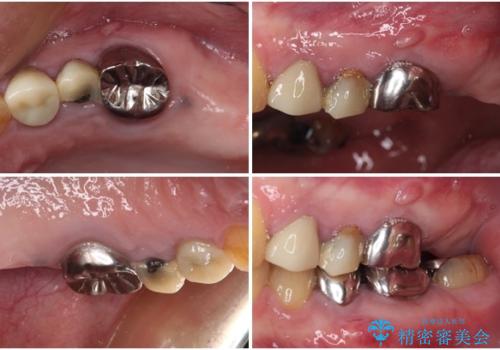

- 上下の奥歯が痛いとのことで来院された患者様です。

診察をしたところ、上下大臼歯の歯肉に排膿路認められたため、根管治療を行い、その後補綴治療を行うこととしました。

また、上顎の欠損部位にはインプラント治療を行うこととしました。

治療を開始したところ、上顎は排膿路が消失し、症状も落ち着きましたが、下顎は一向に改善されませんでした。

改めて診療を行ったところ、歯根破折が認められ、抜歯後にインプラント治療を行うこととしました。